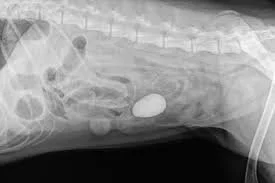

Intestinal Foreign Body in Dogs, When To See The Vet.

Dogs often swallow objects that become stuck in the stomach or intestines. Learn the symptoms of intestinal foreign body obstruction and when emergency veterinary care is needed.